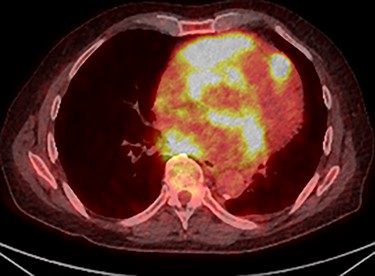

Further staging imaging was recommended by the radiology team. A CT head scan demonstrated no abnormalities, whereas CT chest–abdomen–pelvis (CAP) found significantly enlarged necrotic mediastinal lymph nodes with invasion into the pericardium and heart; bilateral adrenal nodules (suspicious for metastases) and appearances consistent with a lymphoproliferative disorder. The testicular biopsy found large lymphocytes with abundant cytoplasm and prominent nucleoli consistent with a diffuse large B-cell lymphoma (DLBCL). A positron emission tomography (PET) scan was organized at the request of the oncology team (Figs 4 and 5).

PET scan (transverse plane) demonstrating an enhancing lesion encroaching the heart with necrotic lymph nodes.

PET scan (coronal plane) showing intensely metabolically active lymphadenopathy on both sides with extra-nodal involvement through lymphoid tissue, adrenals and muscle.

He was subsequently diagnosed with stage IV (Lugano) DLBCL and underwent the R-CHOP chemotherapy regimen. He has responded well to his oncological treatment.